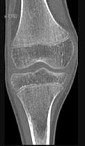

- 单项选择题男,46岁, 膝关节疼痛,结合图像, 最可能的诊断是 ( )

A、骨质硬化

B、骨质疏松

C、骨质软化

D、骨髓瘤

E、转移瘤